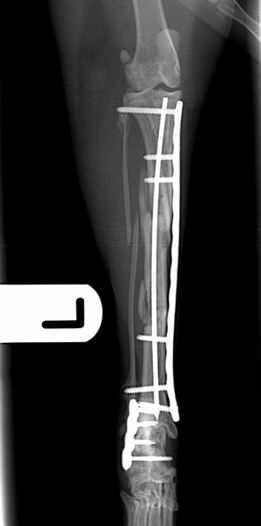

Six weeks post-operative lateral and craniocaudal radiographs         Six weeks post-operative lateral and craniocaudal radiographs

Fig. 3. Six weeks post-operative lateral and craniocaudal radiographs showing complete healing of the calcaneal fracture and excellent progression of healing of the tibial fracture